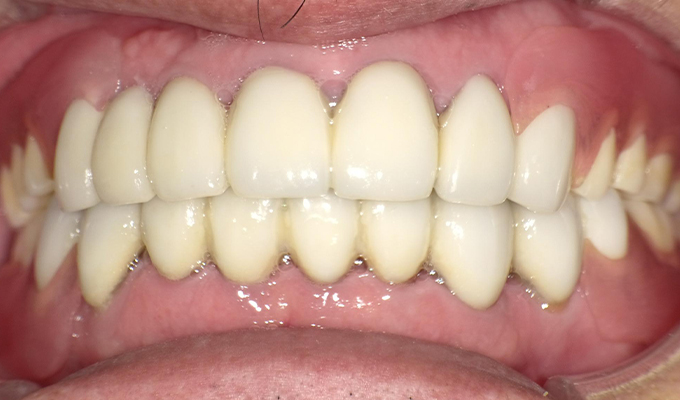

case4ハイブリットセラミックスとナチュラルデンチャーの症例

初診時(2014年)

初回メンテナンス時(2015年)

最新メンテナンス時(2024年)

- 初診時の年齢

- 60代男性(2014年)

- 主訴

- 昔からかみ合わせが悪い。グラグラしている歯がたくさんあるので全体的に治療したい。

- 治療内容

- 全体的に歯周病なのと歯列不正があったため奥歯を抜歯し、歯のない部分にナチュラルデンチャーを入れました。

抜歯にかなり抵抗があったのですがちゃんと咬めるようになりたい!と決心し治療を進めました。上下の前歯にはハイブリットセラミックスを入れ前歯でもしっかり咬めるようにしたので「しっかり咬めるし見栄えもよくなった!」と満足していただけました。継続してメンテナンスもきていただいてます。就寝時はナイトガードもしてしていただいてます。